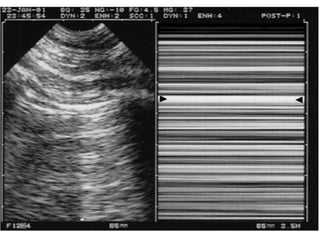

the "seashore sign" (Fig.3).

Absent lung sliding

Exaggerated horizontal artifacts

Loss of comet-tail artifacts

Broadening of the pleural line to a band

The key sonographic signs of

Pneumothorax